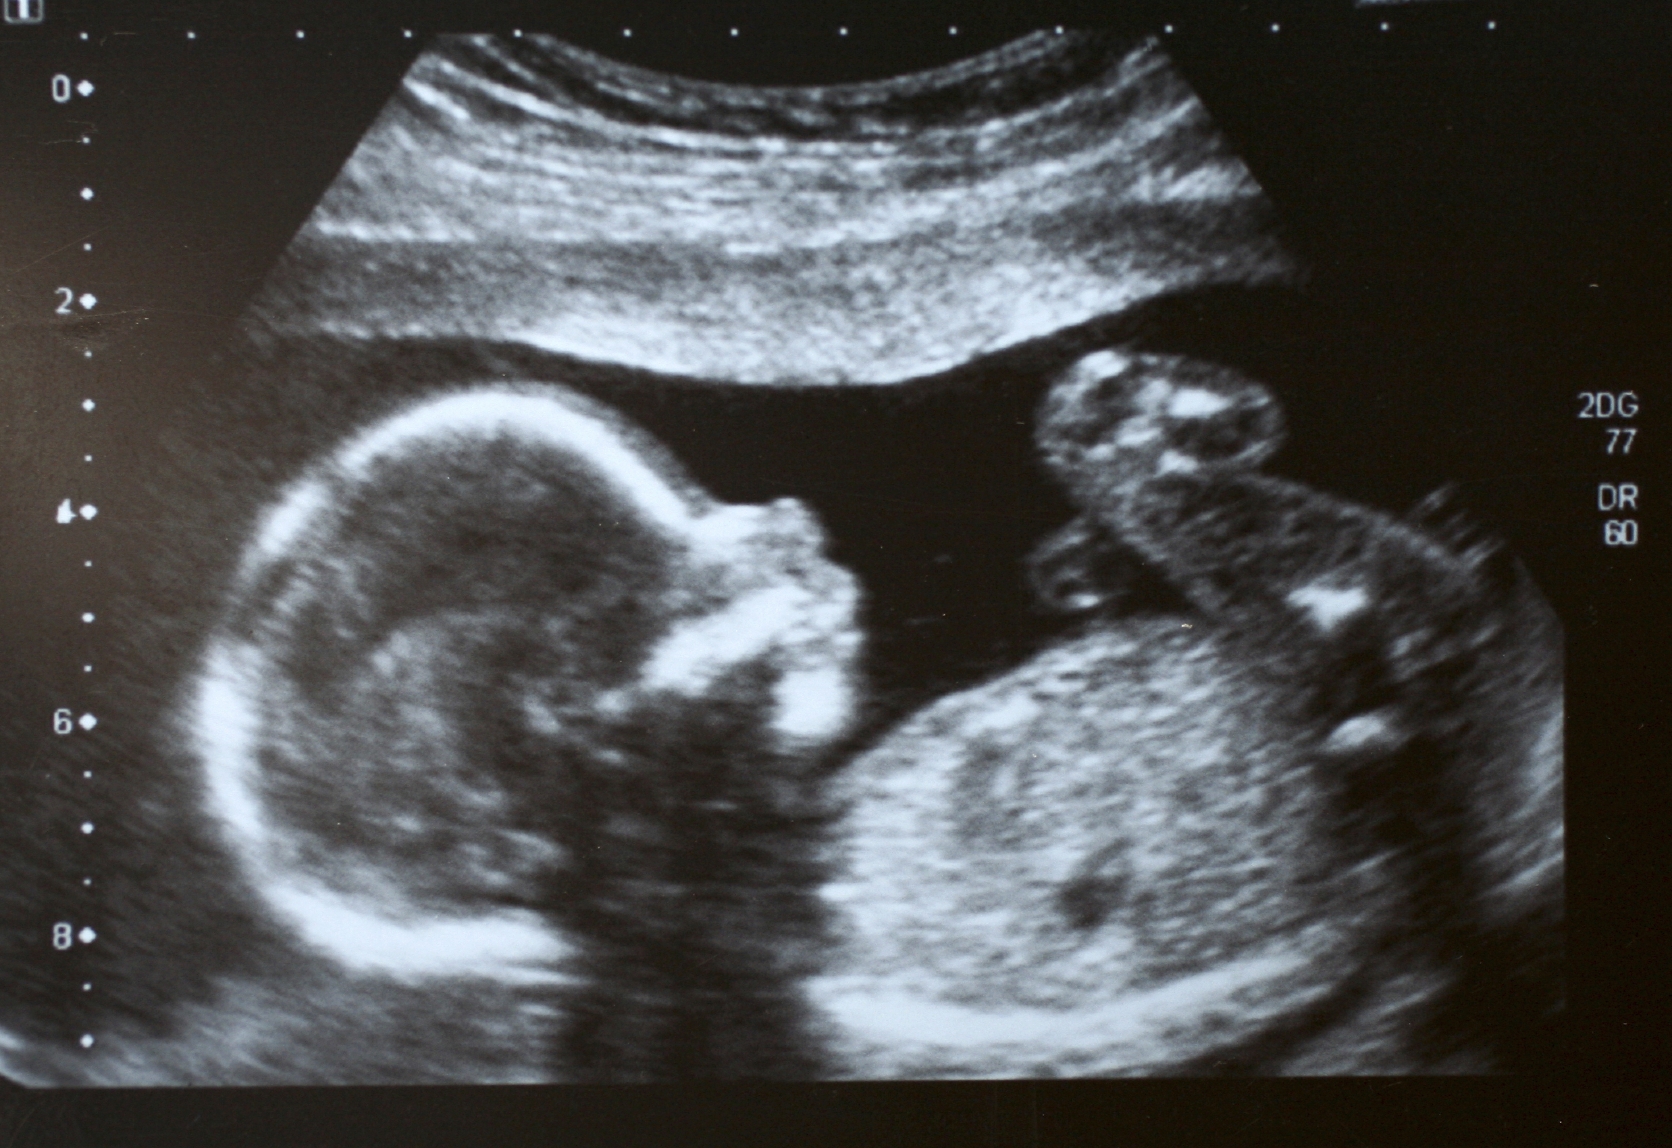

- The nuchal translucency (NT) ultrasound provides important information about a baby’s health early in pregnancy. When combined with blood test results and maternal age, it helps estimate the chance that the baby may have a chromosomal condition, such as Down syndrome (trisomy 21) or trisomy 18.

- Because these measurements are very small, they must be done carefully and consistently. That’s why quality assurance is so important.

Imagine a job where you’re required to make precise measurements (to the tenth of a millimeter), and if they’re not accurate, a pregnant person may be misinformed about their baby’s chance of having Down syndrome. This is the reality for sonographers performing obstetrical scans – their work is meticulous, and the responsibility is immense. Katie Virgin, a sonographer who participated in PSO’s Nuchal Translucency Quality Assurance Program, shares her experience and perspective on this critical work.